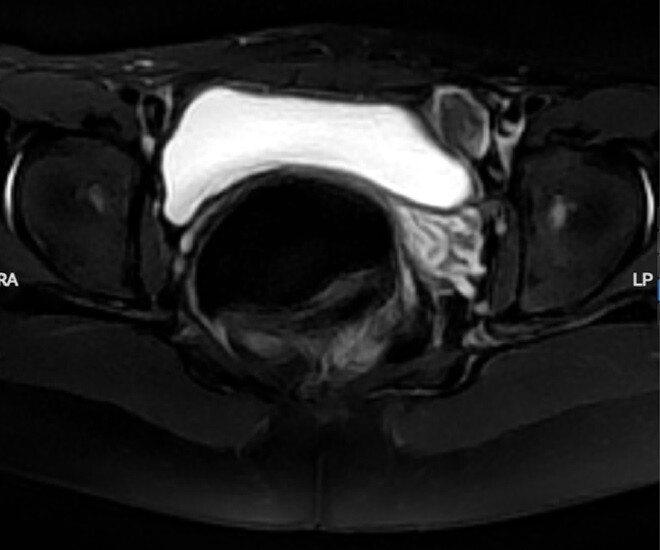

Hình ảnh cho thấy cô gái không có buồng trứng hai bên. Ảnh: BVCC.

Kết quả thăm khám khiến cả gia đình bàng hoàng khi T không có buồng trứng, không có tử cung, đồng thời tồn tại tinh hoàn lạc chỗ trong cơ thể. Bác sĩ nhận định, đây là một bất thường y khoa hiếm gặp, đặt ra nhiều thách thức trong theo dõi sức khỏe, khả năng sinh sản và ổn định tâm lý cho người bệnh.